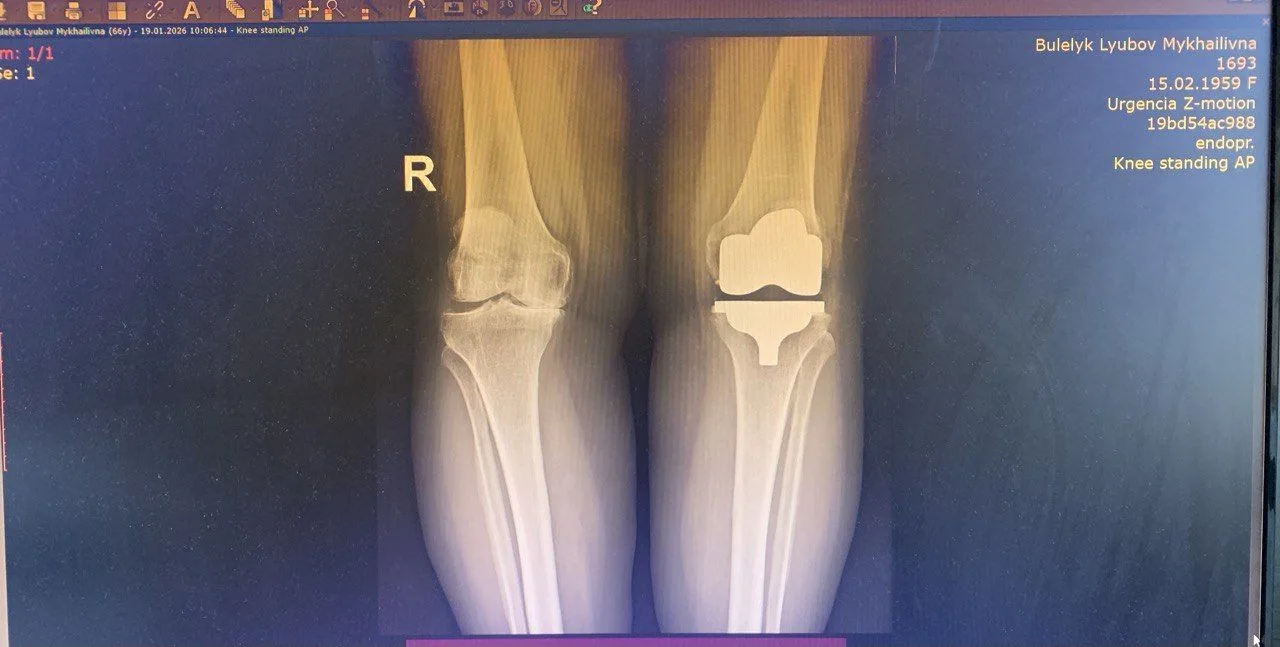

Однією з пацієнток, яку оперували зі застосуванням кінематичного методу, стала Любов Булелик із села Заріччя Делятинської громади. Проблеми з колінами тривали роками, але значно посилилися після коронавірусу. У 2023 році їй підтвердили виражений артроз і рекомендували операцію.

За словами Андрія Шийки, пацієнтка мала виражений артроз із контрактурою колінного суглоба та суттєвим обмеженням рухів. Без оперативного втручання це означало би біль та неможливість ходити і працювати. Зараз пацієнтка успішно проходить реабілітацію.